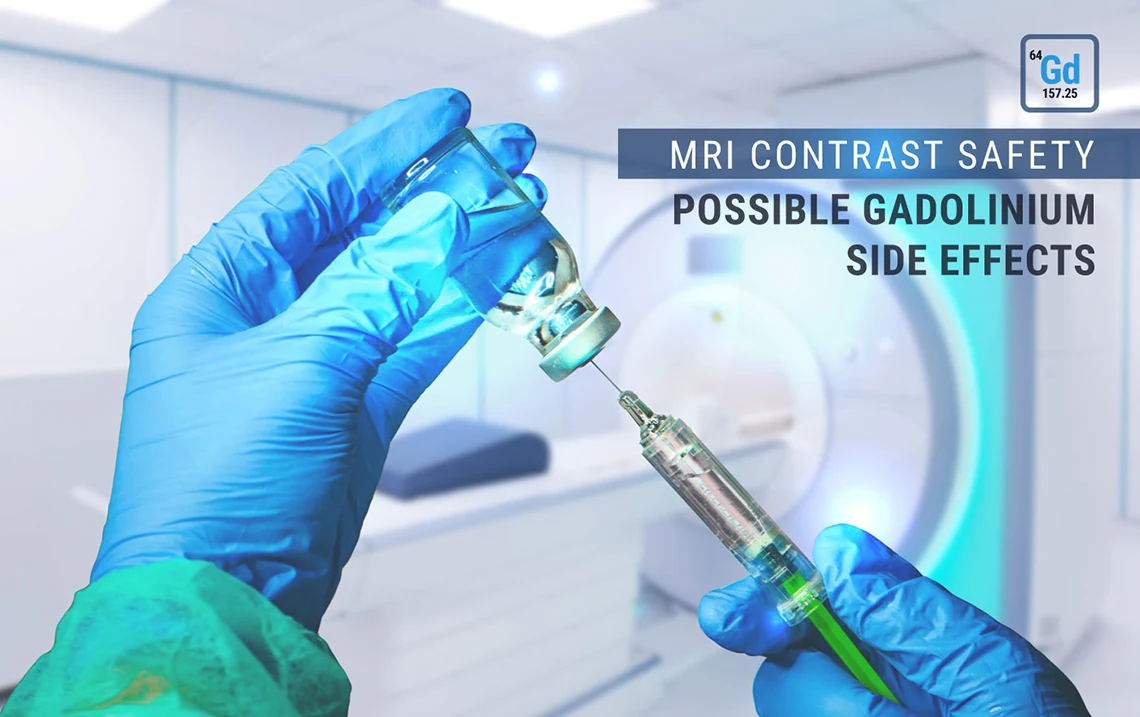

MRI Contrast Safety: Possible Gadolinium Side Effects

MRI Contrast Safety: Possible Gadolinium Side Effects

This article is part of our series of articles on MRI safety for MRI technologists. (Check out our article on the biological effects of MRI here!). This article is focused on MRI contrast media safety, specifically on the possible side effects of gadolinium, preventative measures that you as an MRI technologist can take, and what to do if your patient does experience a side effect after the administration of gadolinium.

MRI Contrast Safety: Overview

Contrast media—gadolinium for MRI—is given to patients in approximately 1 out of every 3 examinations. Most often, it is in the form of an IV injection of a paramagnetic pharmaceutical agent which alters the T1 relaxation of some tissues in order to improve the contrast.